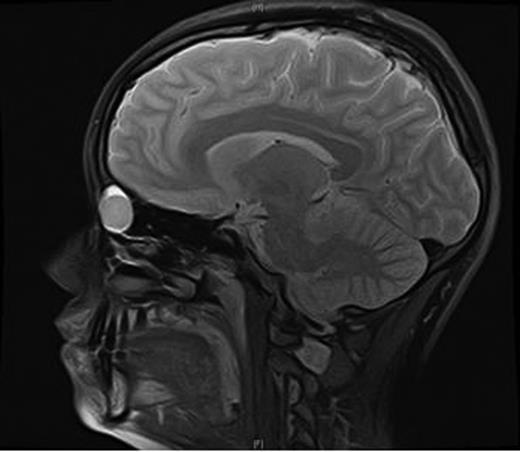

An MRI scan of the orbits showed a well-defined, thin-walled 22 × 16 mm cyst medial to the left orbit containing fatty/proteinaceous material, which was lying within and mildly expanding the left ethmoid air cells (Figs 1–3).